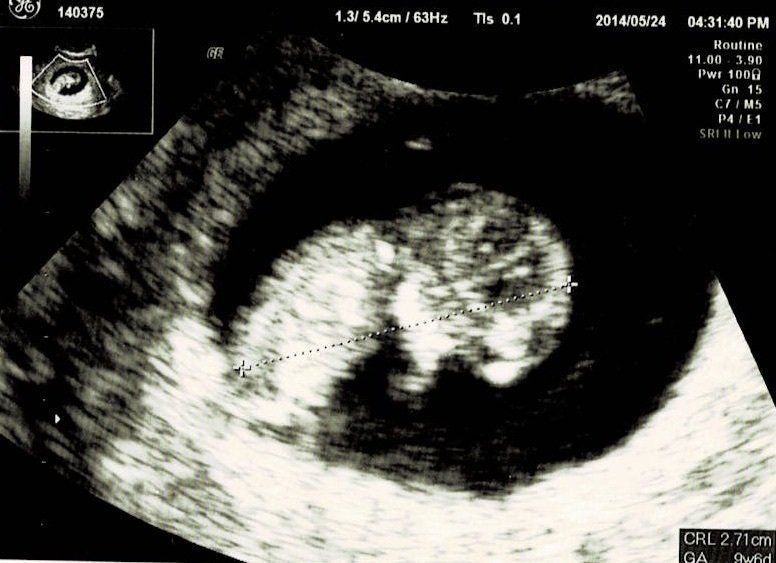

妊娠8週目エコー写真

前の月に生理が止まり、大急ぎで婦人科受診したら“ストレスが原因だっただけ”という出来事があったので、多少生理が遅れていても気にしないでいました。会社の打ち上げに参加した時、ほとんど飲んでいないのにひどく酔っ払ってしまい、体調に違和感を感じました。

翌日妊娠検査薬にトライ。陽性が出たので急いで産婦人科へ。今度こそ妊娠でした!喜びのあまり、この日に母子手帳を受け取りに行ったのを覚えています。

妊娠10週目エコー写真

職場の上司にはこの時点で報告しておきました。「もし、妊娠が継続しなかったら……」ということも考えたのですが、早く伝えたほうが会社にも迷惑がかからないだろうと考えました。このとき、初めて心拍が確認できました。診察後産院の受付に行くと、「赤ちゃんに会える日を楽しみにしています」と書かれたメッセージカードを頂きました。中を開くとエコー写真が。大感激して、今でも大切に取ってあります。